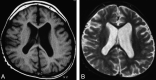

Fig 3.

Type 3. Widespread and scattered white matter abnormalities. FLAIR image of a 12-month-old patient (case 1) with an ATRX mutation of a nucleotide substitution in 5′-UTR. Note high signal intensity on FLAIR/T2WI in the white matter, especially in the peritrigonal area and deep white matter, not in a diffuse but in a widespread and scattered pattern.